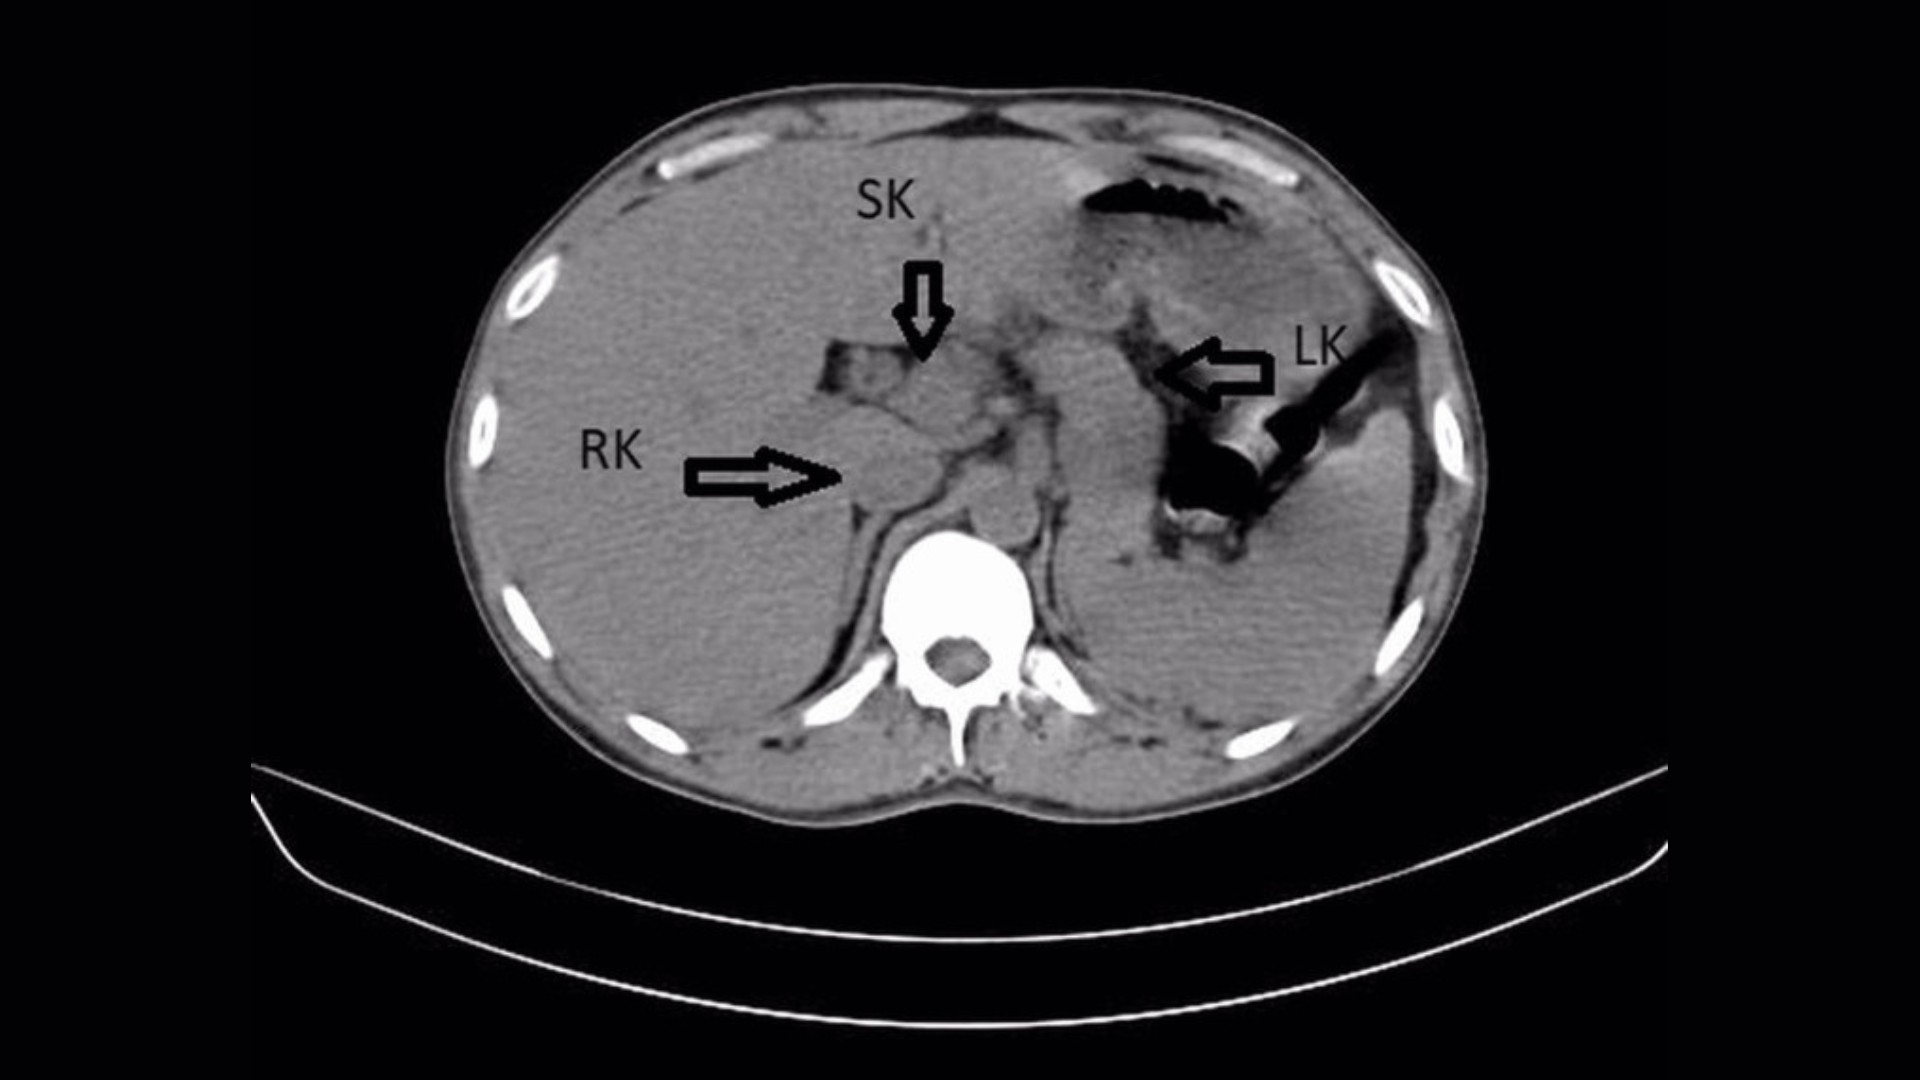

Стандартні діагностичні процедури – ультразвукове дослідження та КТ – виявили не лише інфекцію, а й додаткову нирку, зрощену з правою ниркою, утворюючи характерну форму «підкови». Ця вроджена аномалія виникає в результаті аномального поділу клітин під час внутрішньоутробного розвитку, і хоча часто протікає безсимптомно, вона може призводити до ниркових інфекцій.

У пацієнта також були виявлені відкладення каменів (мінеральних кристалів) у нирках, які можуть закупорювати відтік сечі та посилювати інфекцію. Особливо сильно була торкнута ліва нирка, де камені накопичилися в лівому сечоводі, трубці, що з’єднує нирку з сечовим міхуром.